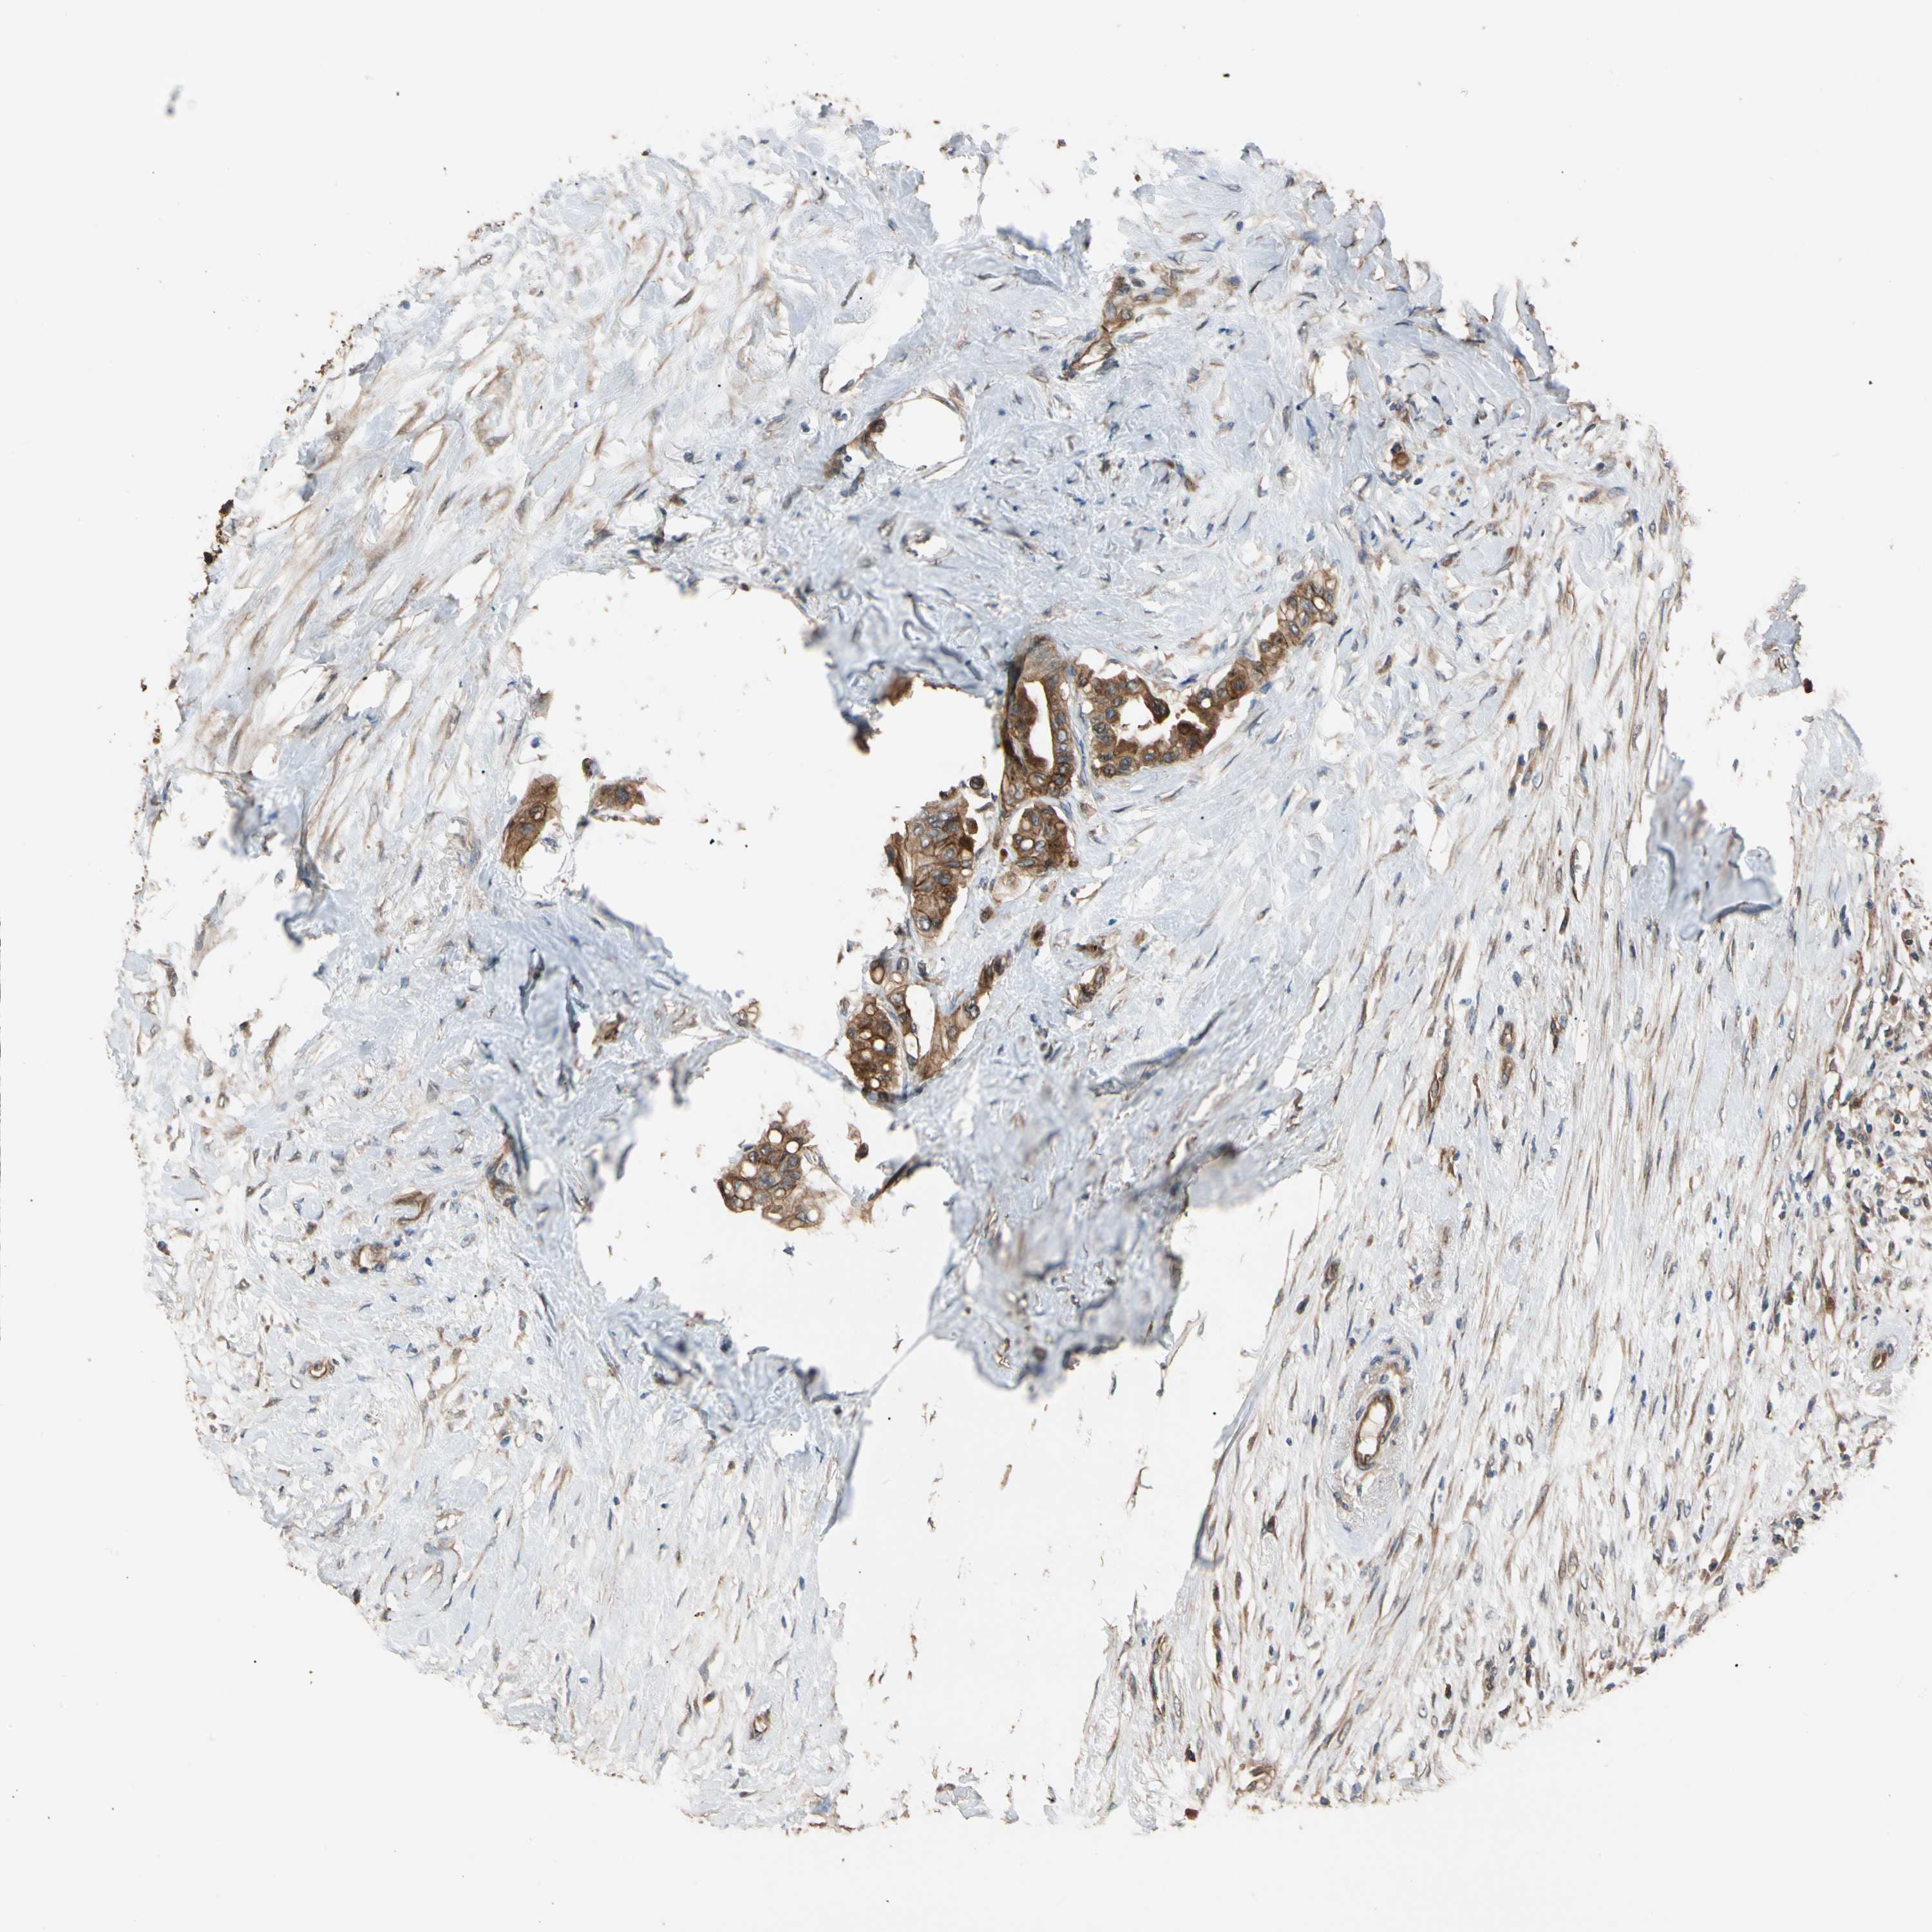

CANCER COLORECTAL CANCER Show tissue menu

Colorectal cancer

Human cancer

Colon adenocarcinoma